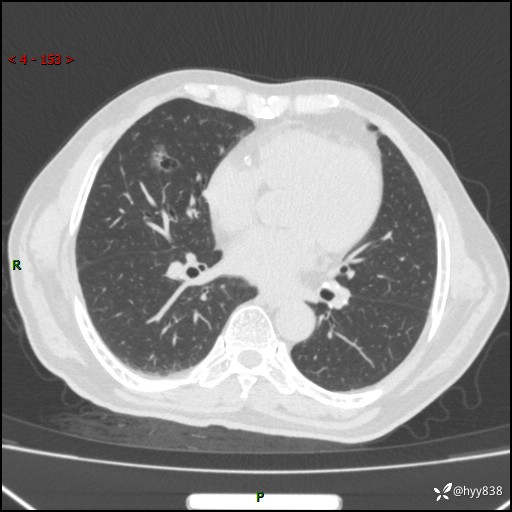

胸部CT复查(2024.7)

CT导向穿刺(靶点---2个结节)